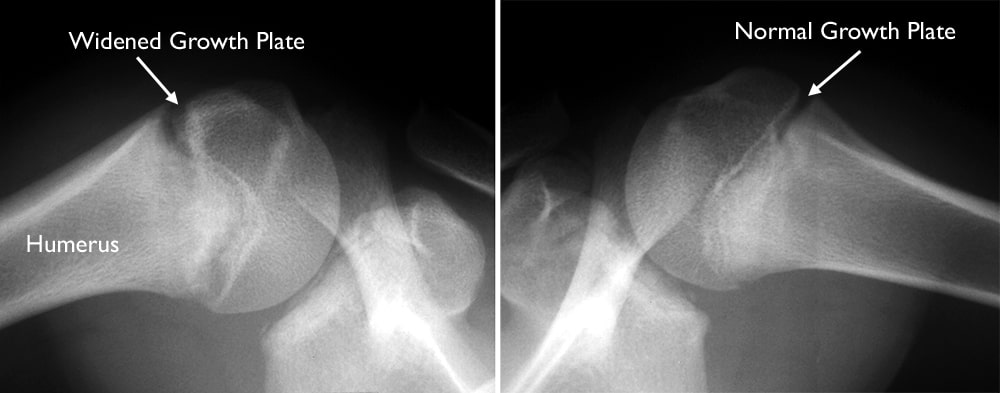

Common examples of sports activities that may cause stress reaction in growth plates include gymnastics and overhand throwing. Gymnasts perform repetitive wrist activities that can lead to stress reaction of the growth plate in the distal radius bone. Young baseball pitchers apply forces across the upper arm bone in their shoulders during the overhand throw. The growth plate in the upper humerus of the shoulder can be damaged and appear widened in an X-ray image.

If the growth plate appears abnormal in an X-ray of a child who participates in a high-risk sport, treatment requires stopping the aggravating activity for 2 to 3 months.

x-rays of normal and widened growth plates in shoulder

(Left) In this X-ray of a child's shoulder, the growth plate has been damaged and appears wider than normal. (Right) An X-ray of the other shoulder shows normal growth plate positioning.